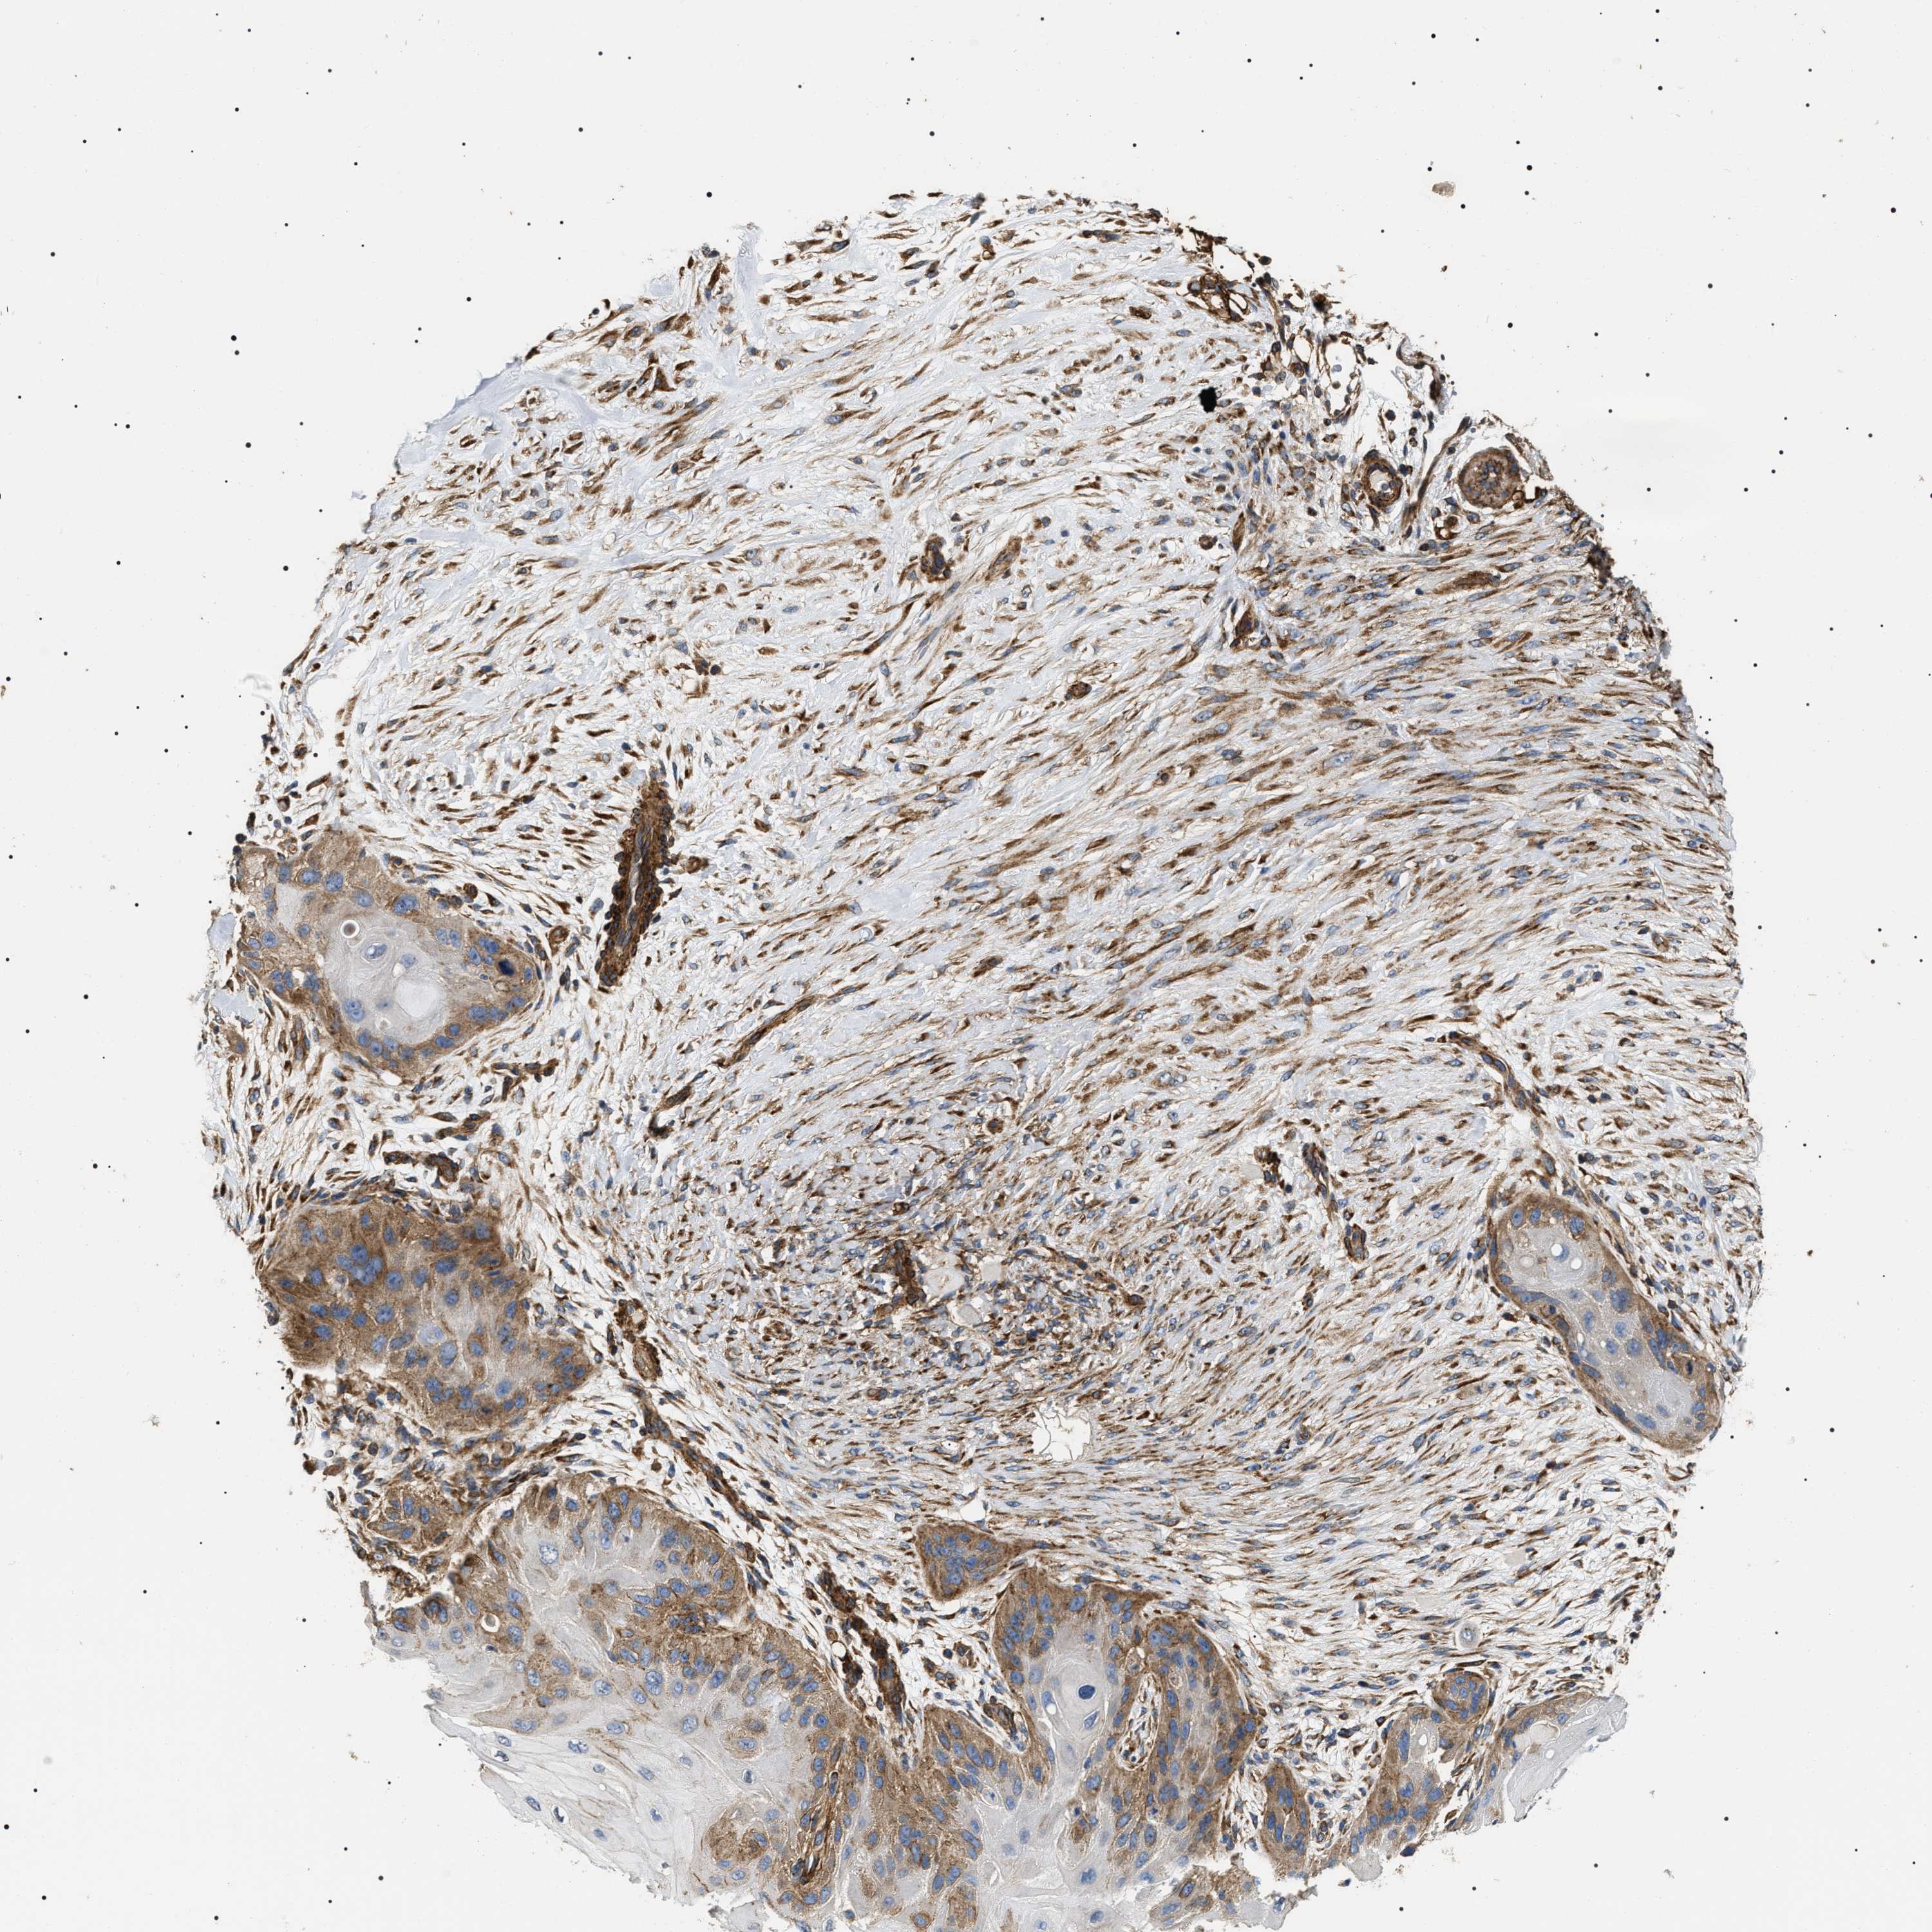

SKIN CANCER - Protein expressioni

A mouse-over function shows sample information and annotation data. Click on an image to view it in a full screen mode. Samples can be filtered based on level of antibody staining by selecting one or several of the following categories: high, medium, low and not detected. The assay and annotation is described here.

Antibody stainingi

Antibody staining in the annotated cell types in the current human tissue is reported as not detected, low, medium, or high, based on conventional immunohistochemistry profiling in selected tissues. This score is based on the combination of the staining intensity and fraction of stained cells.

Each image is clickable and will lead to virtual microscopy that enables deeper exploration of all samples and also displays staining intensity scores, fraction scores and subcellular localization as well as patient and tissue information for each sample.

Antibody HPA020386

Staining

High

Medium

Low

Not detected

Intensity

Strong

Moderate

Weak

Negative

Quantity

>75%

75%-25%

<25%

None

Location

Nuclear

Cytoplasmic/membranous

Cytoplasmic/membranous,nuclear

Basal cell carcinoma